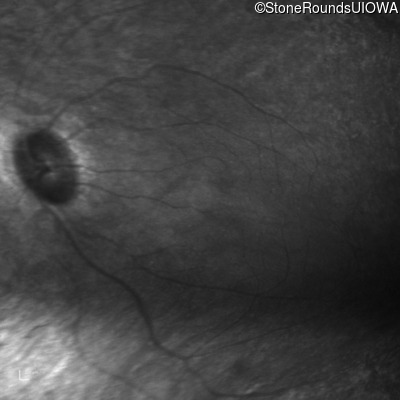

Infrared Fundus Photograph - Right - 20/70 -2

Exemplar